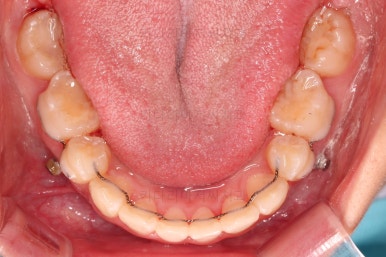

아래 앞니의 높이가 개선된 뒤, 아랫니도 가지런하게 해줍니다.

아랫니도 발치를 하고요.

이 때 대신 선택하는 방법이 어금니를 앞으로 끌고와서 남은 발치 공간을 없애는 방법인데요.

마찬가지로 미니스크류가 사용됩니다.

밀고 당기기와 디테일을 더 정리한 뒤 부산무턱교정치과 마무리를 하게 됩니다.

교합, 과개교합 모두 좋아졌고요.

발치 공간도 깔끔하게 닫히고 종료했습니다.